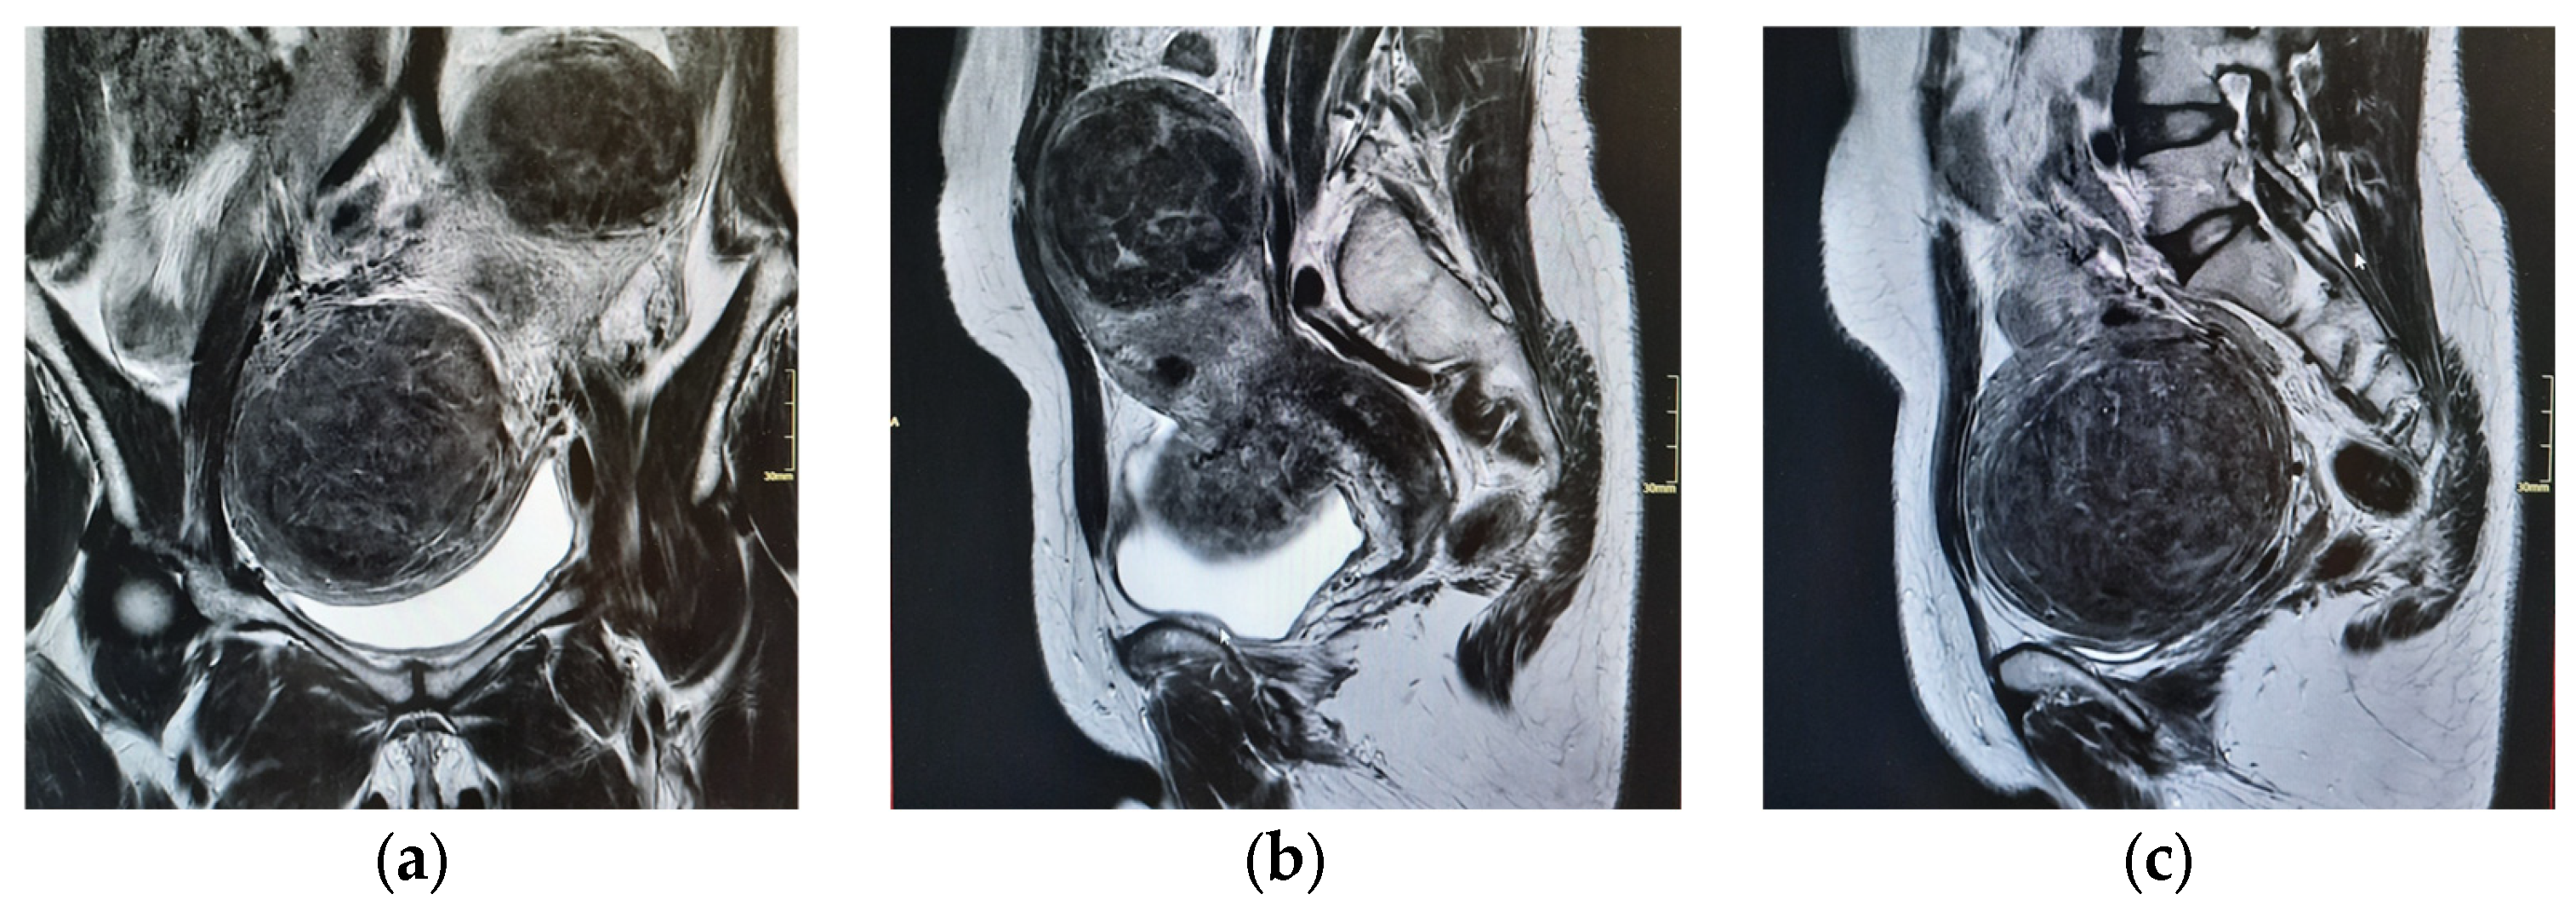

| 15 April 2025 | Pelvic MRI confirms multiple intramural and submucosal fibroids; significant uterine deformation. |